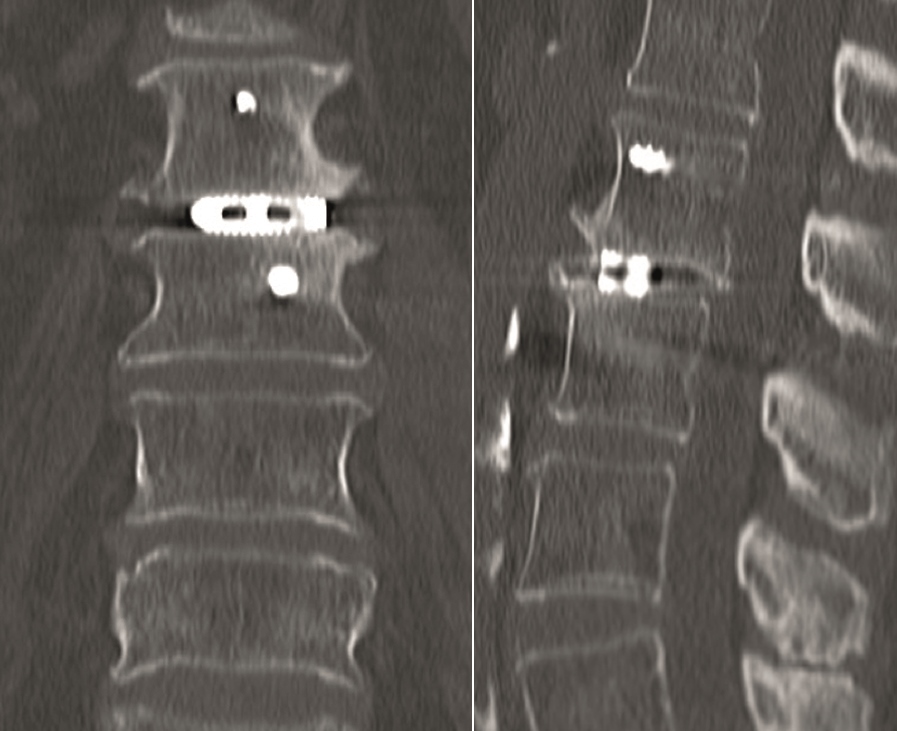

Multilevel facet pathology is shown in Fig 6. Intraoperative and postoperative images are shown (Fig 7-9).

Case 2

A 51-year-old female patient experiencing LBP for 3 years (Fig 10).